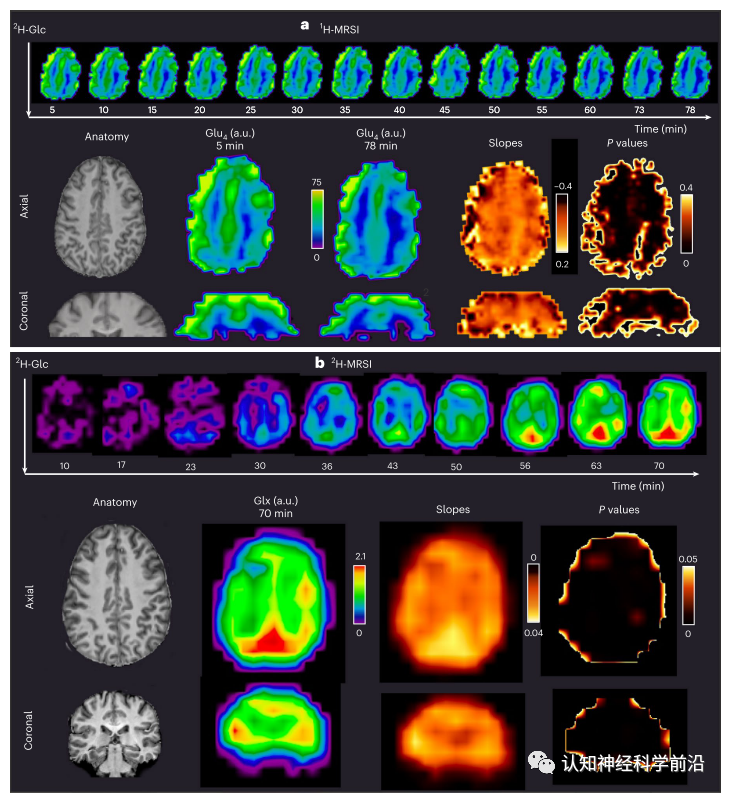

研究发现,质子核磁共振成像在7T下比氘核磁共振成像具有更高的灵敏度、化学特异性和时空分辨率。研究人员在5名志愿者中通过使用氢质子磁共振波谱成像来区分在特定分子位置的氘代的谷氨酸、谷氨酰胺、γ-氨基丁酸和葡萄糖,并同时绘制氘化和非氘化代谢物。氢质子磁共振波谱成像是一种适用于临床可用的磁共振硬件的技术,可以促进大脑中葡萄糖代谢及其在神经系统疾病中的潜在作用的研究。

高时间分辨率下葡萄糖-4和谷氨酸-4时间过程的体素拟合目前,该研究是通过正电子发射断层扫描结合电子计算机断层扫描来完成的,其中患者必须注射少量放射性葡萄糖。然而,这些发现必须在进一步的研究中得到验证,然后才能将研究开发的新的低侵入性方法用于造福患者。通讯作者